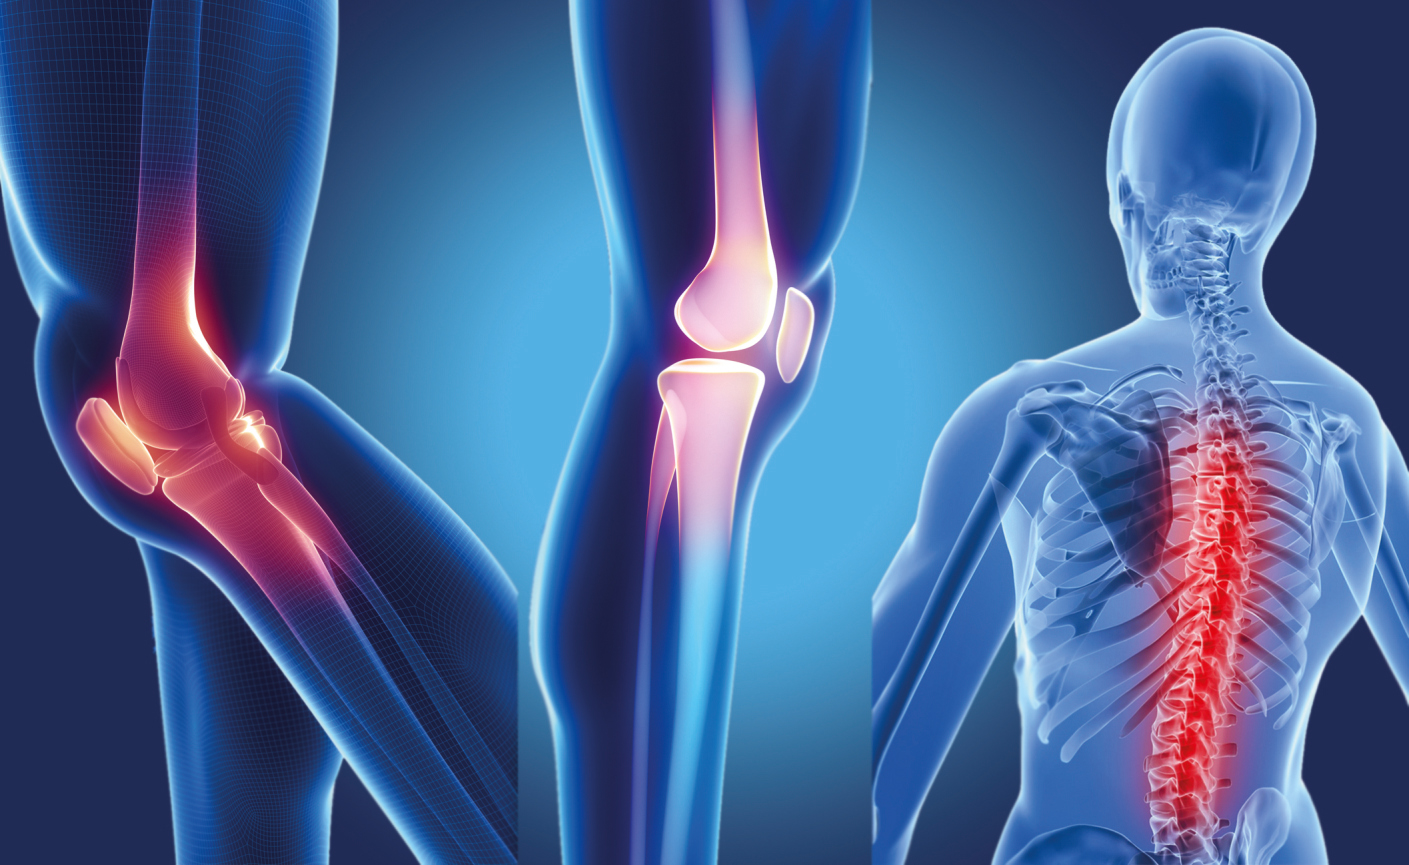

Диаграммы и схемы движения в суставах человека